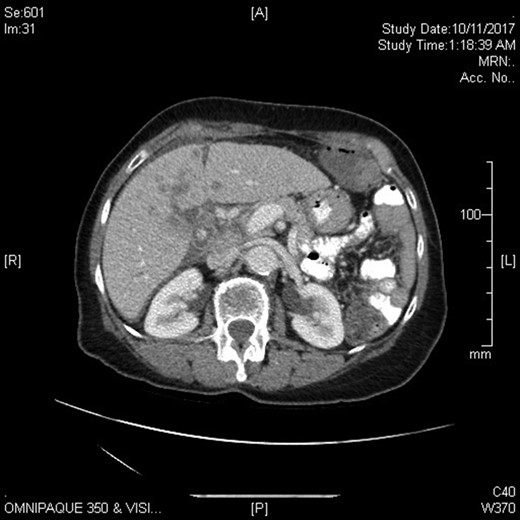

Physical examination revealed a markedly distended abdomen that was otherwise soft and non-tender. She had liver enzymes that were elevated two to five times the upper normal limit. Her tumour markers showed mildly elevated CA-125 and BetaHCG, but normal CEA, AFP and CA19.9. Computed tomography imaging revealed stigmata of chronic cholecystitis and a mass at the gallbladder fossa with evidence of hepatic and peritoneal metastases. The overall appearance was suggestive of metastatic gallbladder carcinoma, though primary hepatocellular carcinoma was considered a possibility given her past history of hepatitis C (Figs 1 and 2).